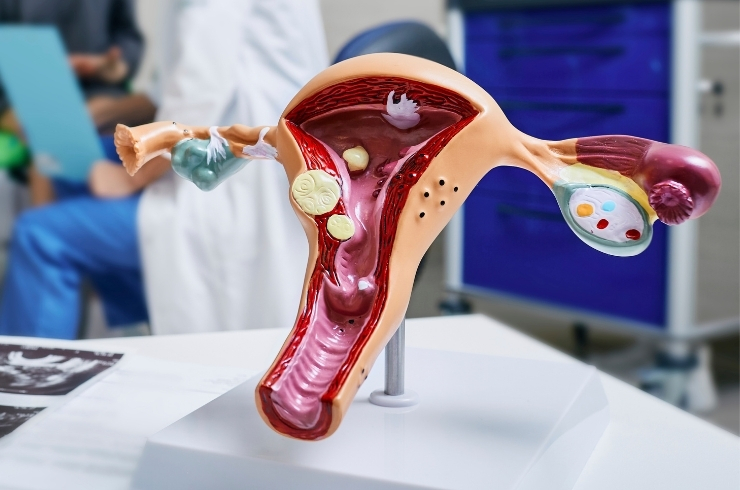

Women’s healthcare including pregnancy care, high-risk obstetrics, deliveries, and gynecological treatments with expert supervision.

Women’s healthcare including pregnancy care, high-risk obstetrics, deliveries, and gynecological treatments with expert supervision.